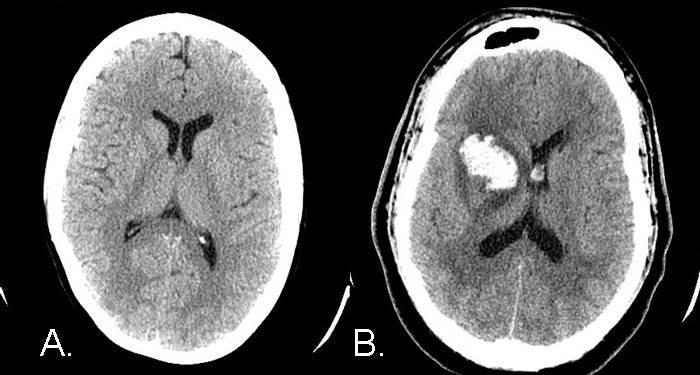

Ictus hemorrágico

Ictus hemorrágico, no isquémico

Asimismo, los autores midieron la angustia psicosocial a partir de cuatro indicadores –percepción de los síntomas del estrés, insatisfacción en la vida, neurosis y depresión– y, una vez alcanzados los resultados, observaron la existencia de una relación inequívoca entre la angustia psicosocial y el ictus hemorrágico –que no con el ictus isquémico.